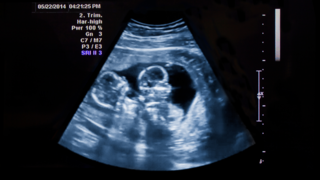

How is the Diagnosis of TTTS done?

Doctors diagnose TTTS using ultrasound and Doppler scans. These tests are used to check fluid levels, bladder filling, and blood flow in each baby.